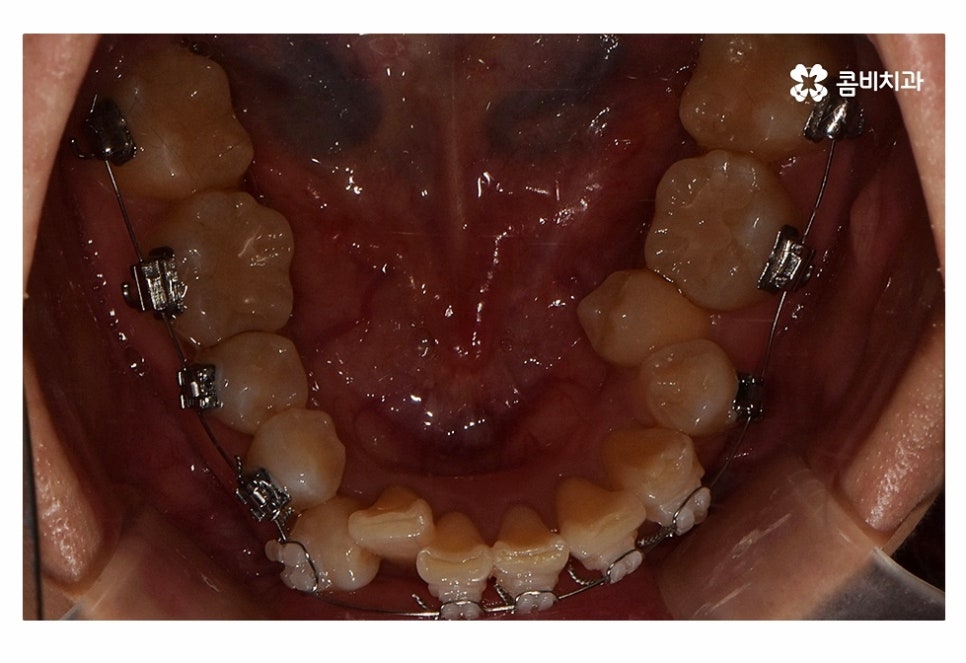

사진으로 보시는 환자분의 경우 윗니에 비해

아랫니가 좀 더 불규칙하다는 것을 알 수 있는데요.

오늘 사례의 환자분은 아랫니의 치열이 불규칙하고

교합을 고려할 때 전체교정을 진행해야 했지만